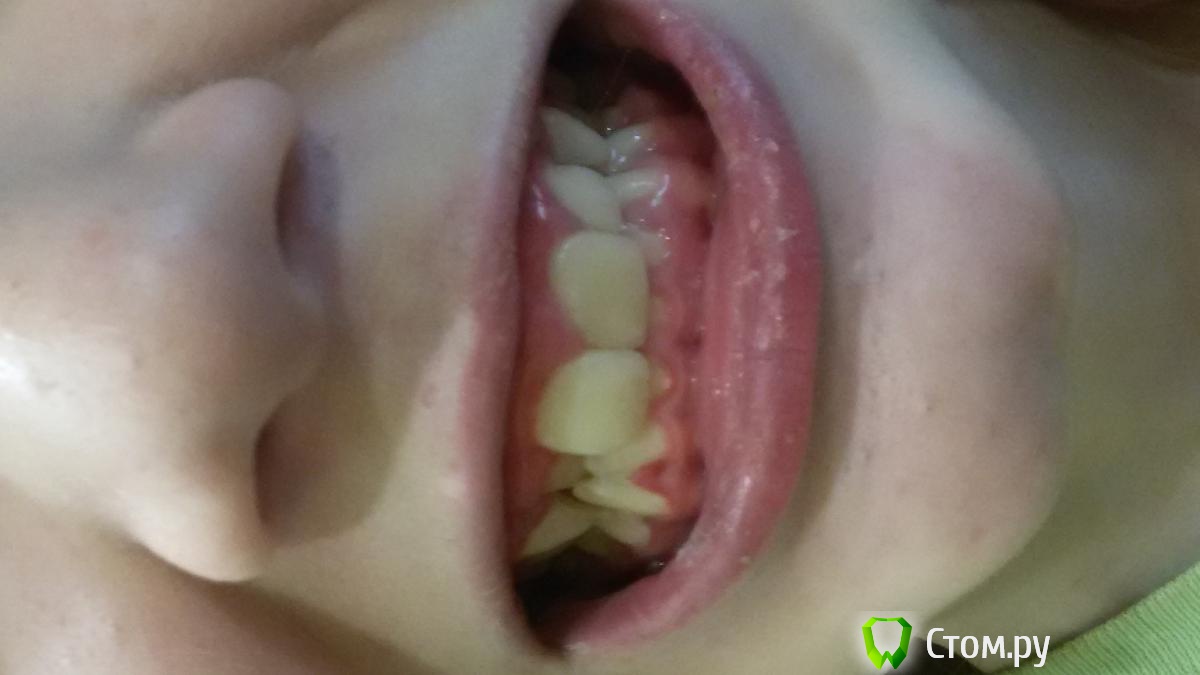

Элько Опубликовано 21 августа, 2014 Поделиться Опубликовано 21 августа, 2014 Здравствуйте! Девочка 12.5 лет . Доктор, сделав панорамный снимок, дала направление на удаление 24 зуба и через два месяца на прием с дальнейшим удалением с другой стороны . Так как клыкам нет места совсем на челюсти они лезут сверху вторым рядом. над 24 уже прорезался а с другой стороны еще нет. Подскажите удаление здоровых коренных зубов как в дальнейшей жизни скажется? И возможны ли другие варианты лечения. Ссылка на комментарий

Ayrat_zub Опубликовано 21 августа, 2014 Поделиться Опубликовано 21 августа, 2014 Здравствуйте! Девочка 12.5 лет . Доктор, сделав панорамный снимок, дала направление на удаление 24 зуба и через два месяца на прием с дальнейшим удалением с другой стороны . Так как клыкам нет места совсем на челюсти они лезут сверху вторым рядом. над 24 уже прорезался а с другой стороны еще нет. Подскажите удаление здоровых коренных зубов как в дальнейшей жизни скажется? И возможны ли другие варианты лечения.упражнение для шеи решили устроить?)) снмики первернутые как попало) можно буз удаения 4-ок, еще одного снимка не хватает Ссылка на комментарий

Ayrat_zub Опубликовано 22 августа, 2014 Поделиться Опубликовано 22 августа, 2014 Я не знаю почему они в разные стороны у меня все ровно было а выгрузилось так .А какой еще нужен снимок? и как без удаления ? Я так понимаю с удалением проще все поставить на место, но как это аукнется в дальнейшем? снимок ТРГ, и кт в области верхних клыков, удалить скорее всего рпидется, но не 4-ки, а зубы мудрости, хотя на верхней челсюти есть варианты) сделайте более четкие фото) по поводу ортодорнта-http://forum.stom.ru/topic/4747-posovetuite-ortodonta-v-gorode-n/ Ссылка на комментарий